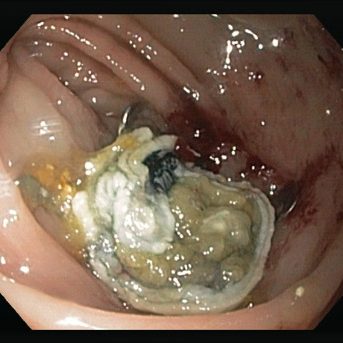

Procedural sequence EFTR of a recurrent sessile adenoma (non-lifting sign) in the descending colon

* Source: Prof. K. Caca and Dr. A. Schmidt, Klinikum Ludwigsburg, Dept. of Internal Medicine, Gastroenterology, Hemato-Onkology, Diabetes and Infektious Diseases, Germany

De novo resection after incomplete polypectomy in the descending colon (early carcinoma)

Resection of a relapsed adenoma (HGIEN) in the descending colon (non-lifting sign)